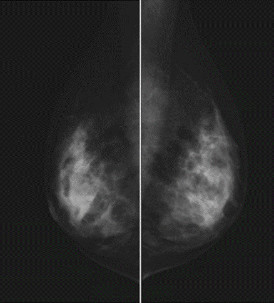

乳腺撮影装置

FUJIFILM社 AMULET Innovality

フラットパネル搭載した乳腺撮影装置でありスクリーニングからバイオプシーまでこなします。また、診断用コンソールにはコンピューター支援システム(image checker D)を搭載します。

当院ではマンモグラフィー検診精度管理中央委員会の講習を受講し認定された医師2名を有します。また、施設認定並びに放射線技師の認定も得られるよう準備しています。

CAD System なぜCADを使用するのか?

マンモグラムの解釈は簡単ではありません。正常な乳房組織は女性それぞれによって大きく異なります。

同じ女性でも、検査時期によって、あるいは同じ月の別の日に検査を行っても、違いがあります。乳房構造の複雑な画像、疾病を示す一部の特徴の微妙さ正確な検出を行う必要性、ケースの数の多さ、疲労、これらが組み合わされることにより偽陰性読影につながります。

ImageCheckerシステムは、医療画像におけるスペルチェッカーのようなものです。

二次読影が必要と思われる領域に対して放射線科医の注意を喚起することにより、観察上の見落としによる偽陰性読影の数を低減する助けとするためのシステムです。

※石灰化は▲、石灰化は*にて表されます。